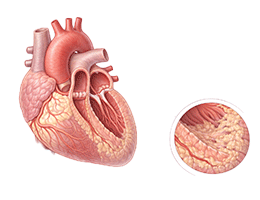

심근경색 (Myocardial Infarction)

협심증 (Angina Pectoris)

심근병증 (Cardiomyopathy)

심부전 (Heart Failure)

비대성심근병증 (Hypertrophic Cardiomyopathy)

확장성심근병증 (Dilated Cardiomyopathy)

울혈성심부전 (Congestive Heart Failure)

심근염 (Myocarditis)